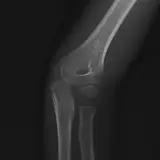

Over 2,100 interactive radiology cases, curated by radiologists for your level of training. Scroll, window, and view cases full screen — just like on PACS. Click linked findings in each writeup to jump straight to them on the image. Cases include sample reports, a focused discussion section, original illustrations, and videos.

Casos totalmente interactivos con las herramientas que esperaría de un PACS: scroll, ventana, zoom, pan, mediciones, ROI y modo de pantalla completa.

• Anotaciones enlazadas

Anotaciones extensas resaltan los hallazgos clave directamente sobre los casos. Haga clic en los hallazgos enlazados dentro de la descripción del caso para saltar a su ubicación exacta en el estudio.

Aprenda con eficiencia gracias a hallazgos de imagen anotados e ilustraciones